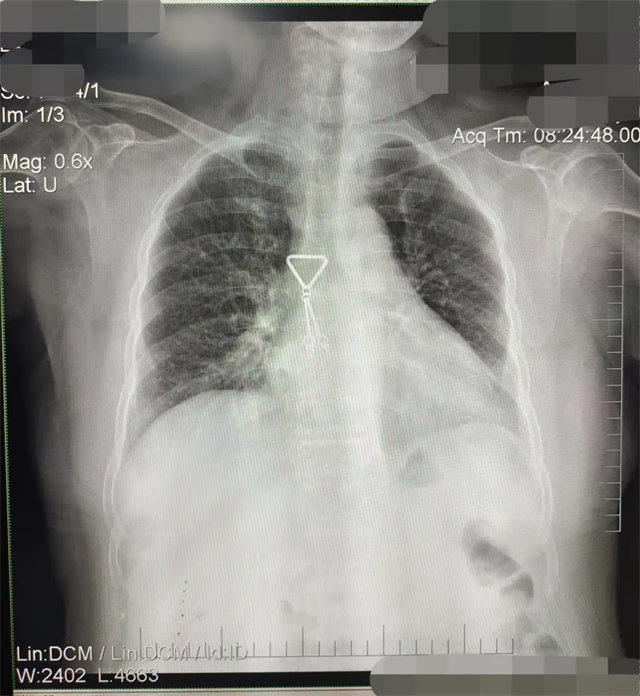

缺陷:肩胛骨未完全拉離肺野,吸氣不完全,存在金屬偽影遮擋,略有聳肩,且肺尖顯示不好,圖像顆粒感較強,管電流量不夠,信噪比偏低。

解決:去除金屬物品后,按標(biāo)準(zhǔn)體位,使患者雙肩旋前與前胸一并緊貼成像件,適當(dāng)調(diào)高mAs,然后深吸氣后屏氣曝光。